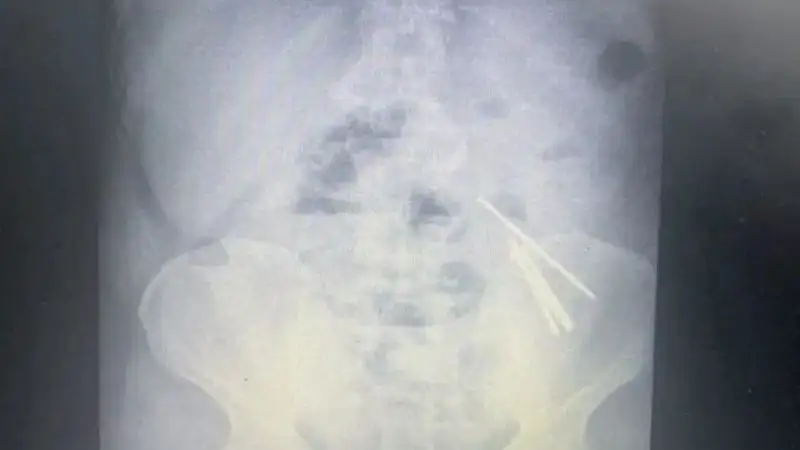

В Алматинской области мужчина, страдающий шизофренией, проглотил 14 гвоздей размером до 10 см, сообщает Zakon.kz.

Врачи-хирурги извлекли из тонкого кишечника 39-летнего мужчины в общей сложности 14 гвоздей размером до 10 см.

По словам заведующего хирургическим отделением Марата Абжанова, диагностика подобных случаев основана на рентгенографической визуализации.

Врач рассказал, что при удалении 14 гвоздей размером 10 см был поражен тонкий кишечник, в котором имелись перфорации. Послеоперационный период протекал без осложнений.